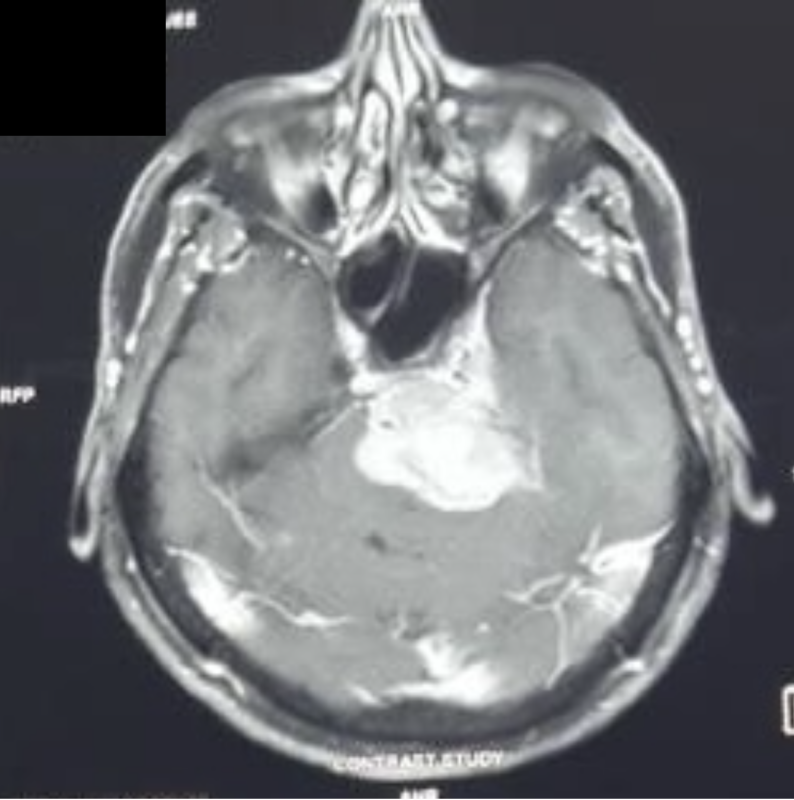

錐体斜台部髄膜腫

久々のインド・コルカタでの症例です。 今回は、動脈瘤クリッピングのレジェンド・佐野公俊先生とともに現地を訪問し、手術に臨みました。 私が担当したのは、いつも通り頭蓋底腫瘍。今回は(今回も、ですね)錐体斜台部髄膜腫です。 以前にも述べましたが、福島孝徳先生をもってして「最も難しい手術」とされる領域です。 限られた時間の中、transpetrosal approachを用いて、付着部を残しつつ腫瘍本体の摘出を行いました。